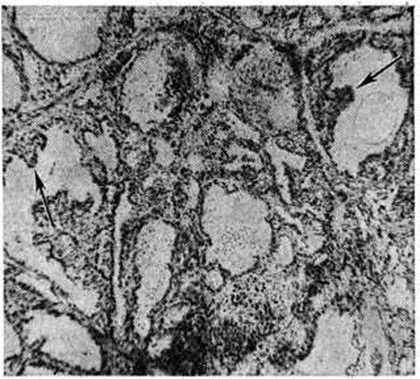

При отсутствии предварительного лечения в щитовидной железе чаще выявляются диффузные изменения с полиморфизмом фолликулов; их контуры неправильны, просвет может быть щелевидным или звездчатым. Фолликулярный эпителий цилиндрический, нередко многослойный, образует в просвете фолликулов разрастания папилломатозного типа (рисунок 1). Коллоид жидкий, слабо эозинофилен, содержит большое количество резорбционных вакуолей. Кровеносные сосуды переполнены кровью. В интерфолликулярной соединительной ткани обнаруживаются скопления лимфоцитов с образованием лимфоидных фолликулов (рисунок 2). Эпителиальные клетки нередко деструктивно изменены, слущиваются и могут быть обнаружены в просвете фолликулов. Приведённые изменения, возникающие в интактной щитовидной железе, получили название базедовского зоба.

Рис. 1.

Микропрепарат щитовидной железы при диффузном токсическом зобе: стрелками указаны выросты эпителия папилломатозного типа, растущего в полость фолликула; × 300.